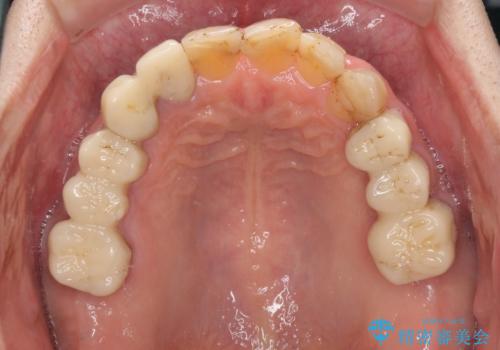

全体的に中等度の歯周病と診断されたため、歯周外科処置やインプラントによる咬合回復から進めて行き、矯正治療による歯列改善を行った後にオールセラミッククラウンにて補綴することとしました。

矯正治療を希望して来院されましたが、歯周病を併発していたため、矯正治療開始前の処置が非常に多くなりました。特に歯槽骨の再生治療を行ったため、外科処置後の静置期間が長くなり、4年弱の治療期間となりました。

治療後には咬みやすさだけでなく、前歯が大変審美的に仕上がり、患者様には大変満足していただきました。